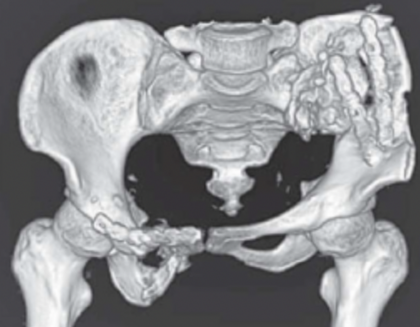

骨盆CT三维重建影像显示骨盆环形状不规则,骨盆明显倾斜(图2)。